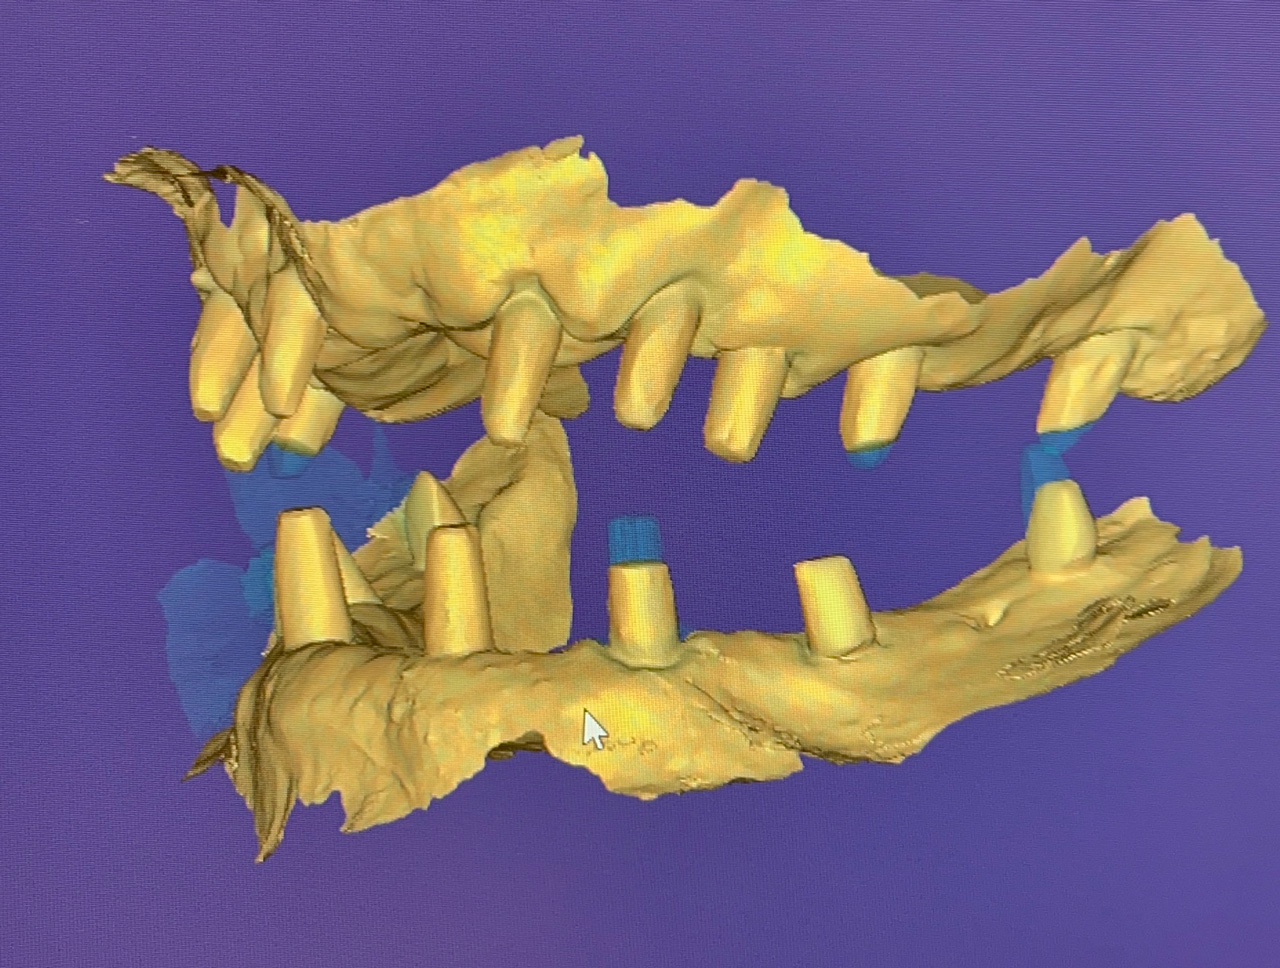

Teljes szájüregi rehabilitáció két lépésben

Ismét egy teljes szájüregi rehabilitáció két lépésben. Először az alsó fogak lettek kihúzva és azonnal implantálva, híddal ellátva, majd később a felső. IHDE svájci azonnal terhelhető implantátumok és cirkónium hidak. Dr. Kelemen Péter és a Symbion Fogtechnika közös munkája.